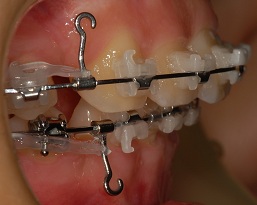

옆면 사진